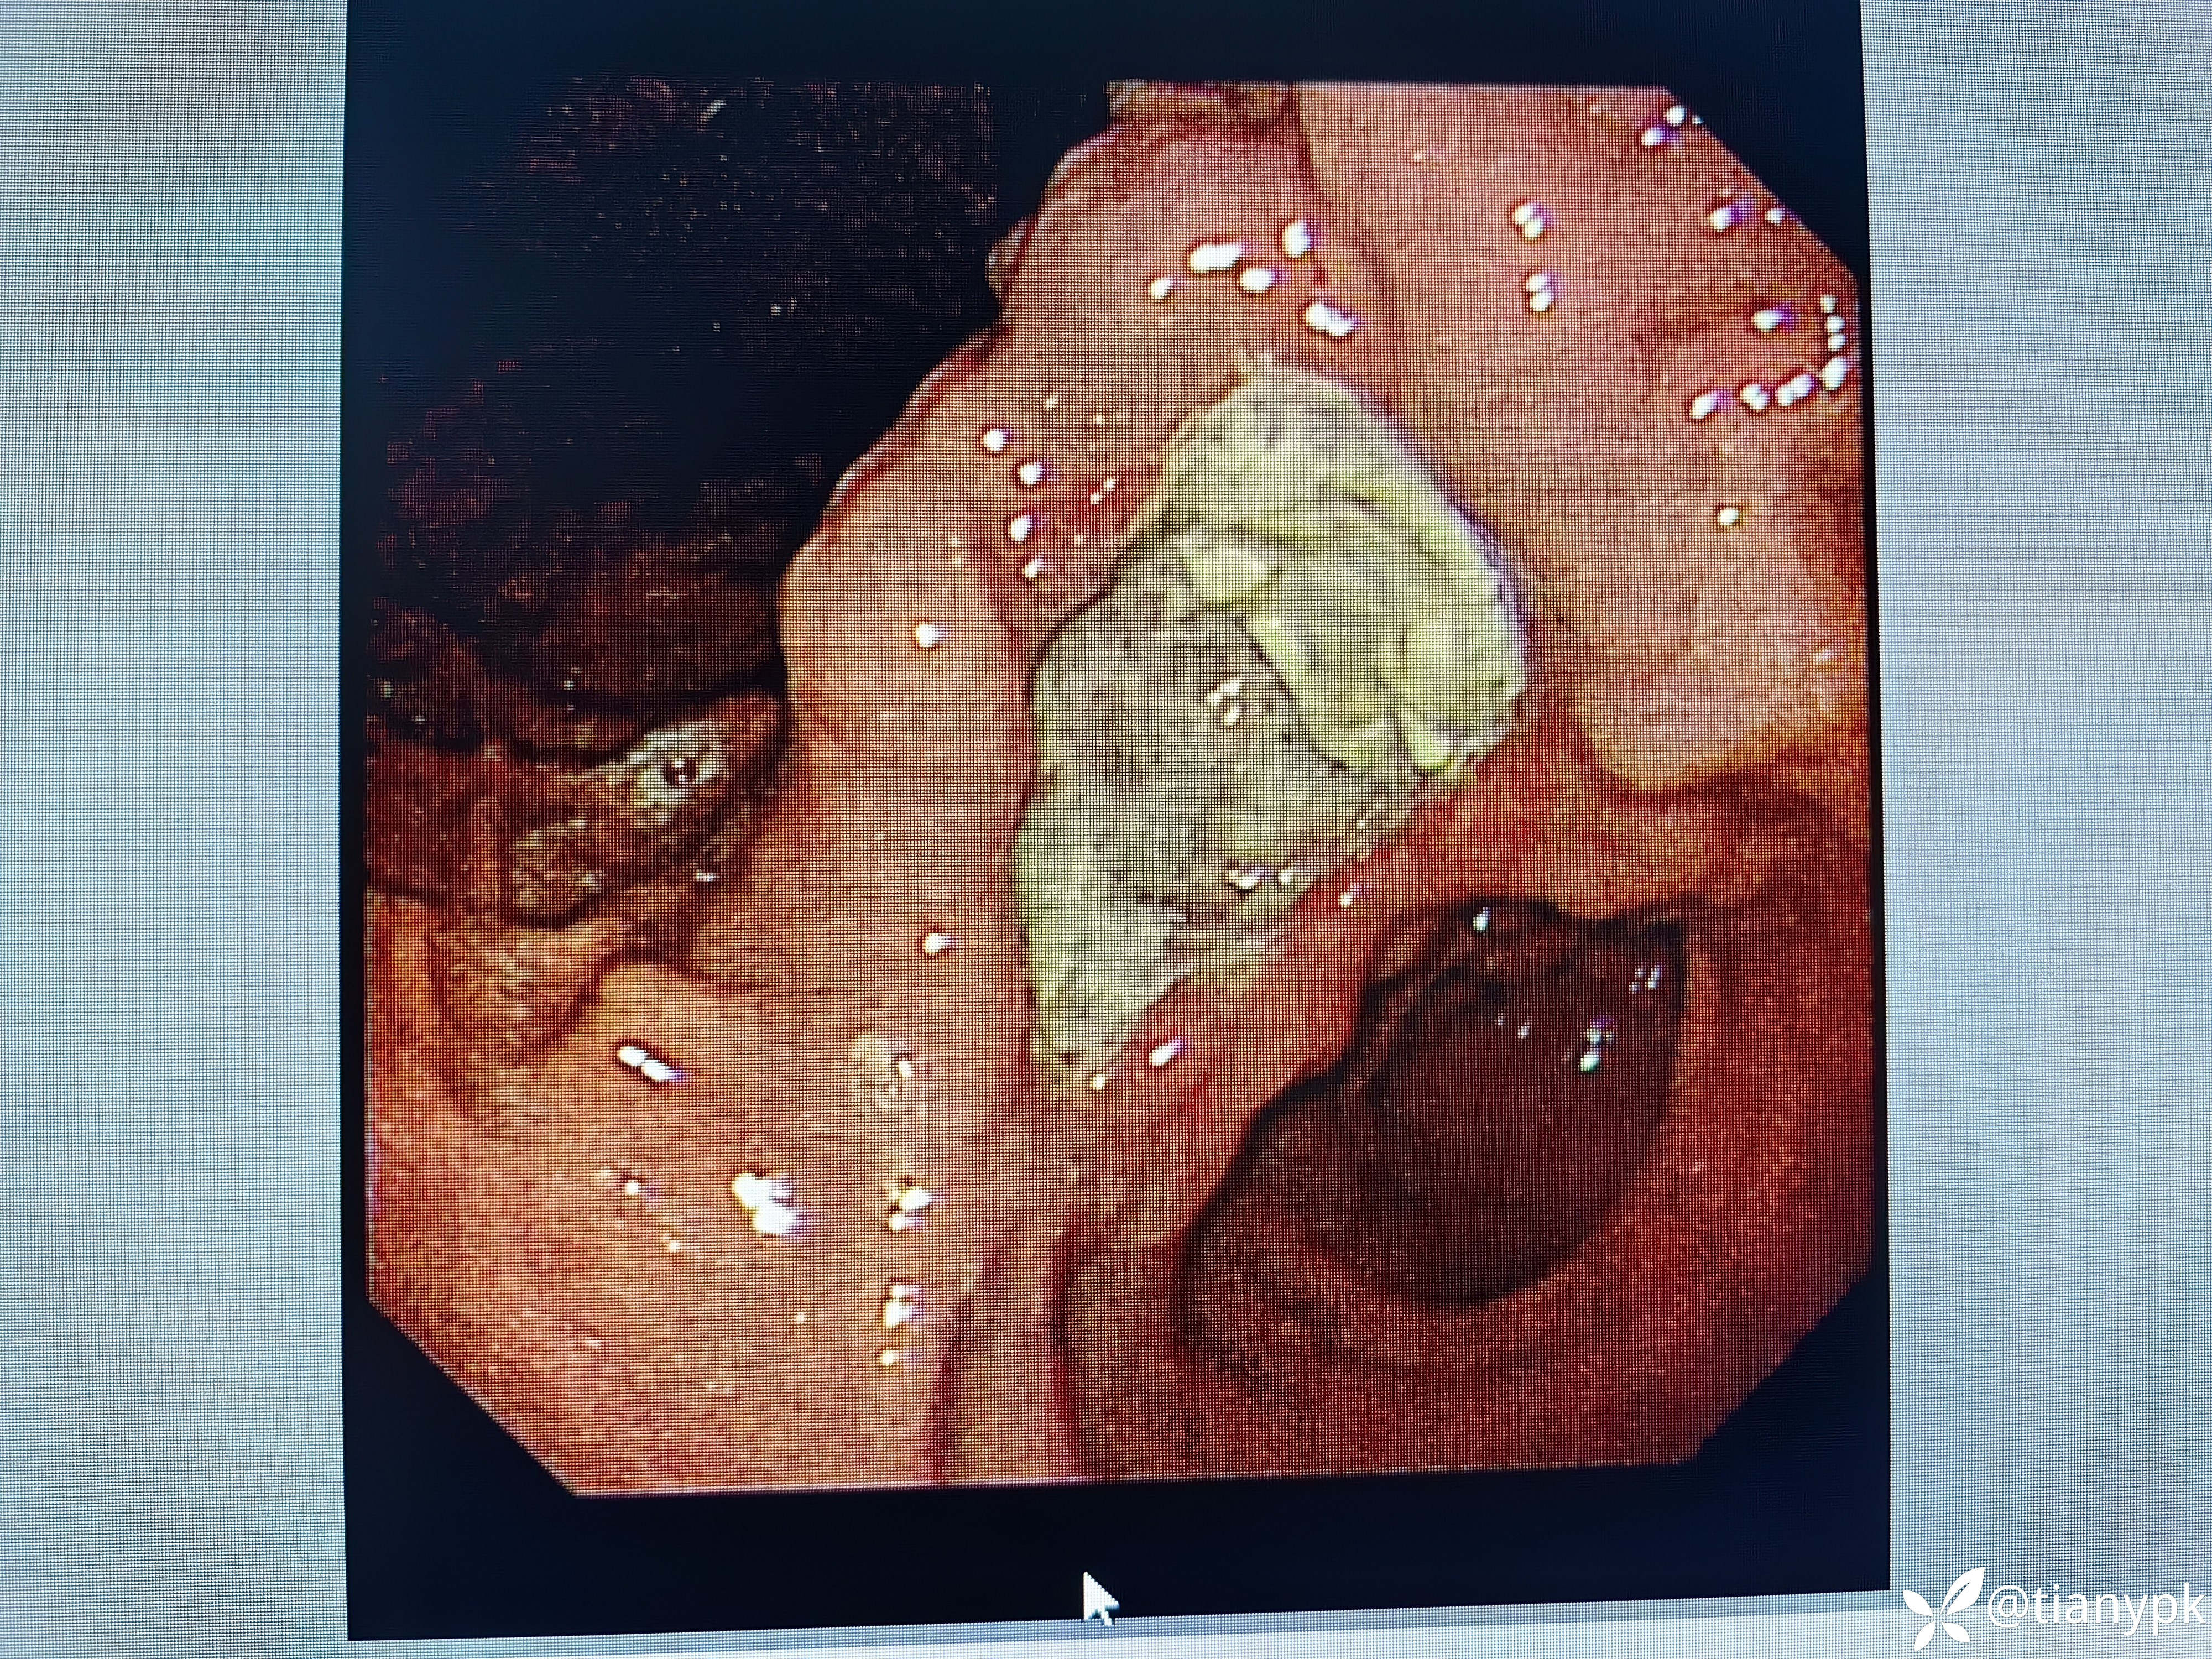

男性,54岁。

主诉:中上腹隐痛一周余伴大便发黑。

既往有乙肝,长期抗病毒治疗,否认近期明显消瘦。

胃镜检查如下:

胃角见巨大溃疡,良性?恶性?

活检大家一般取几块?